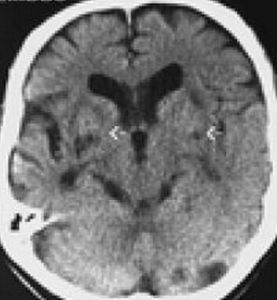

3.腦電圖有瀰漫性g波和8波。CT掃描顯示側腦室、第三腦室擴大和腦溝增寬。核素腦血流圖測定可有腦血流量減少。